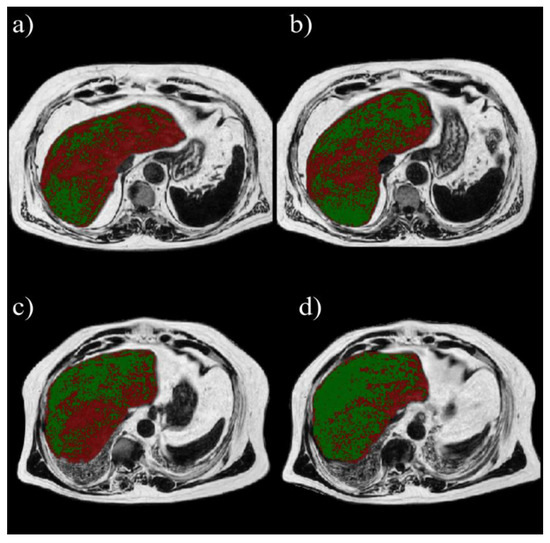

2.2. Liver Fat Content

2.2.2. MRI

2.3.2. Volumetric Analysis of Liver Fat